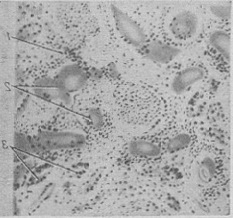

Зміни нирок при М. б. носять вторинний характер. Патогенетично мієломна нефропатія («мієломна нирка») пов'язана в першу чергу з проходженням через нирковий фільтр патологічних білкових тіл, що утворюються в результаті специфічної секреторної активності мієломних клітин. Таким чином, мієломна нефропатія являє собою справжній «нефроз виділення». Клінічно вона характеризується протеїнурією (див.) при відсутності гематурії, набряків, гіпертонії і ретинопатії. В подальшому розгортається картина ниркової недостатності: олігурія з низькою питомою вагою сечі і прогресуюча азотемія з явищами уремії, аж до розвитку фібринозного перикардиту і коми, завершується летальним результатом. Причиною розвитку уремії (див.) при мієломної хвороби є не стільки зміни клубочкового апарату, скільки порушення сечовиділення по канальцям, буквально забитих білковими масами (рис. 10). Відому роль у зниженні ниркової фільтрації при М. б. можуть грати і внепочечные фактори: артеріальна гіпотонія і гиперонкия плазми (внаслідок гиперпротеинемии). Ці фактори при наявності обтурації канальців нирки патологічними білками можуть призвести до різкої олігурії, аж до повної анурії.

![]() Рис. 10. Парапротеинемічний нефроз при мієломної хвороби: склероз і круглоклеточная інфільтрація (1) интерстиция нирки; просвіти канальців розтягнуті, заповнені білковими масами (2), епітелій атрофичен; 3 - регенерація епітелію звивистих канальців.  |